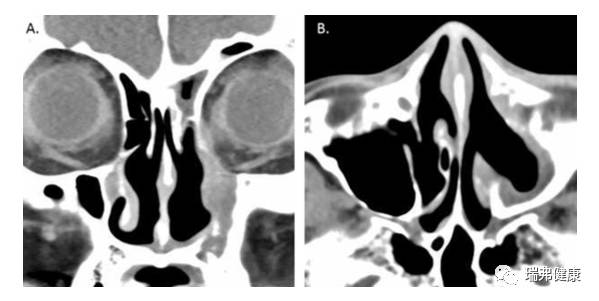

患者质子治疗2年后鼻旁窦CTA图为冠状缝切面,B为轴向剖面